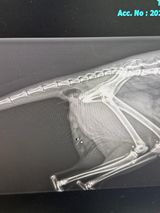

Can any vets shed any light on what this is on the xray by the tail?

Looks like an area of fluid or gas radiopacity either underlying the base of the tail or within the rectal/pelvic area. The back of the pelvis (ischium) looks a bit dubious for a possible fracture (e.g. if the cat was hit by a car) so the opacity could also be related to that, although it would need a wound communicating to the outside (or inside the rectum) for that gas area to be present which the vet would probably have seen. The X-rays not the best quality though!

Given that it's an entire male cat and it's around it's back end, could be a cat bite abscess that has developed but I'd expect the vet to have noticed that already if so (and would presumably be why they gave it antibiotics).

History of missing for a while could mean all sorts of hidden issues esp with regards to trauma. Not sure if the xray "balloon" was jusr rectal gas or a pocket of gas, don't think it was purulent fluid as that would likely be flocculent in appearance, but simple patient investigation would answer that.